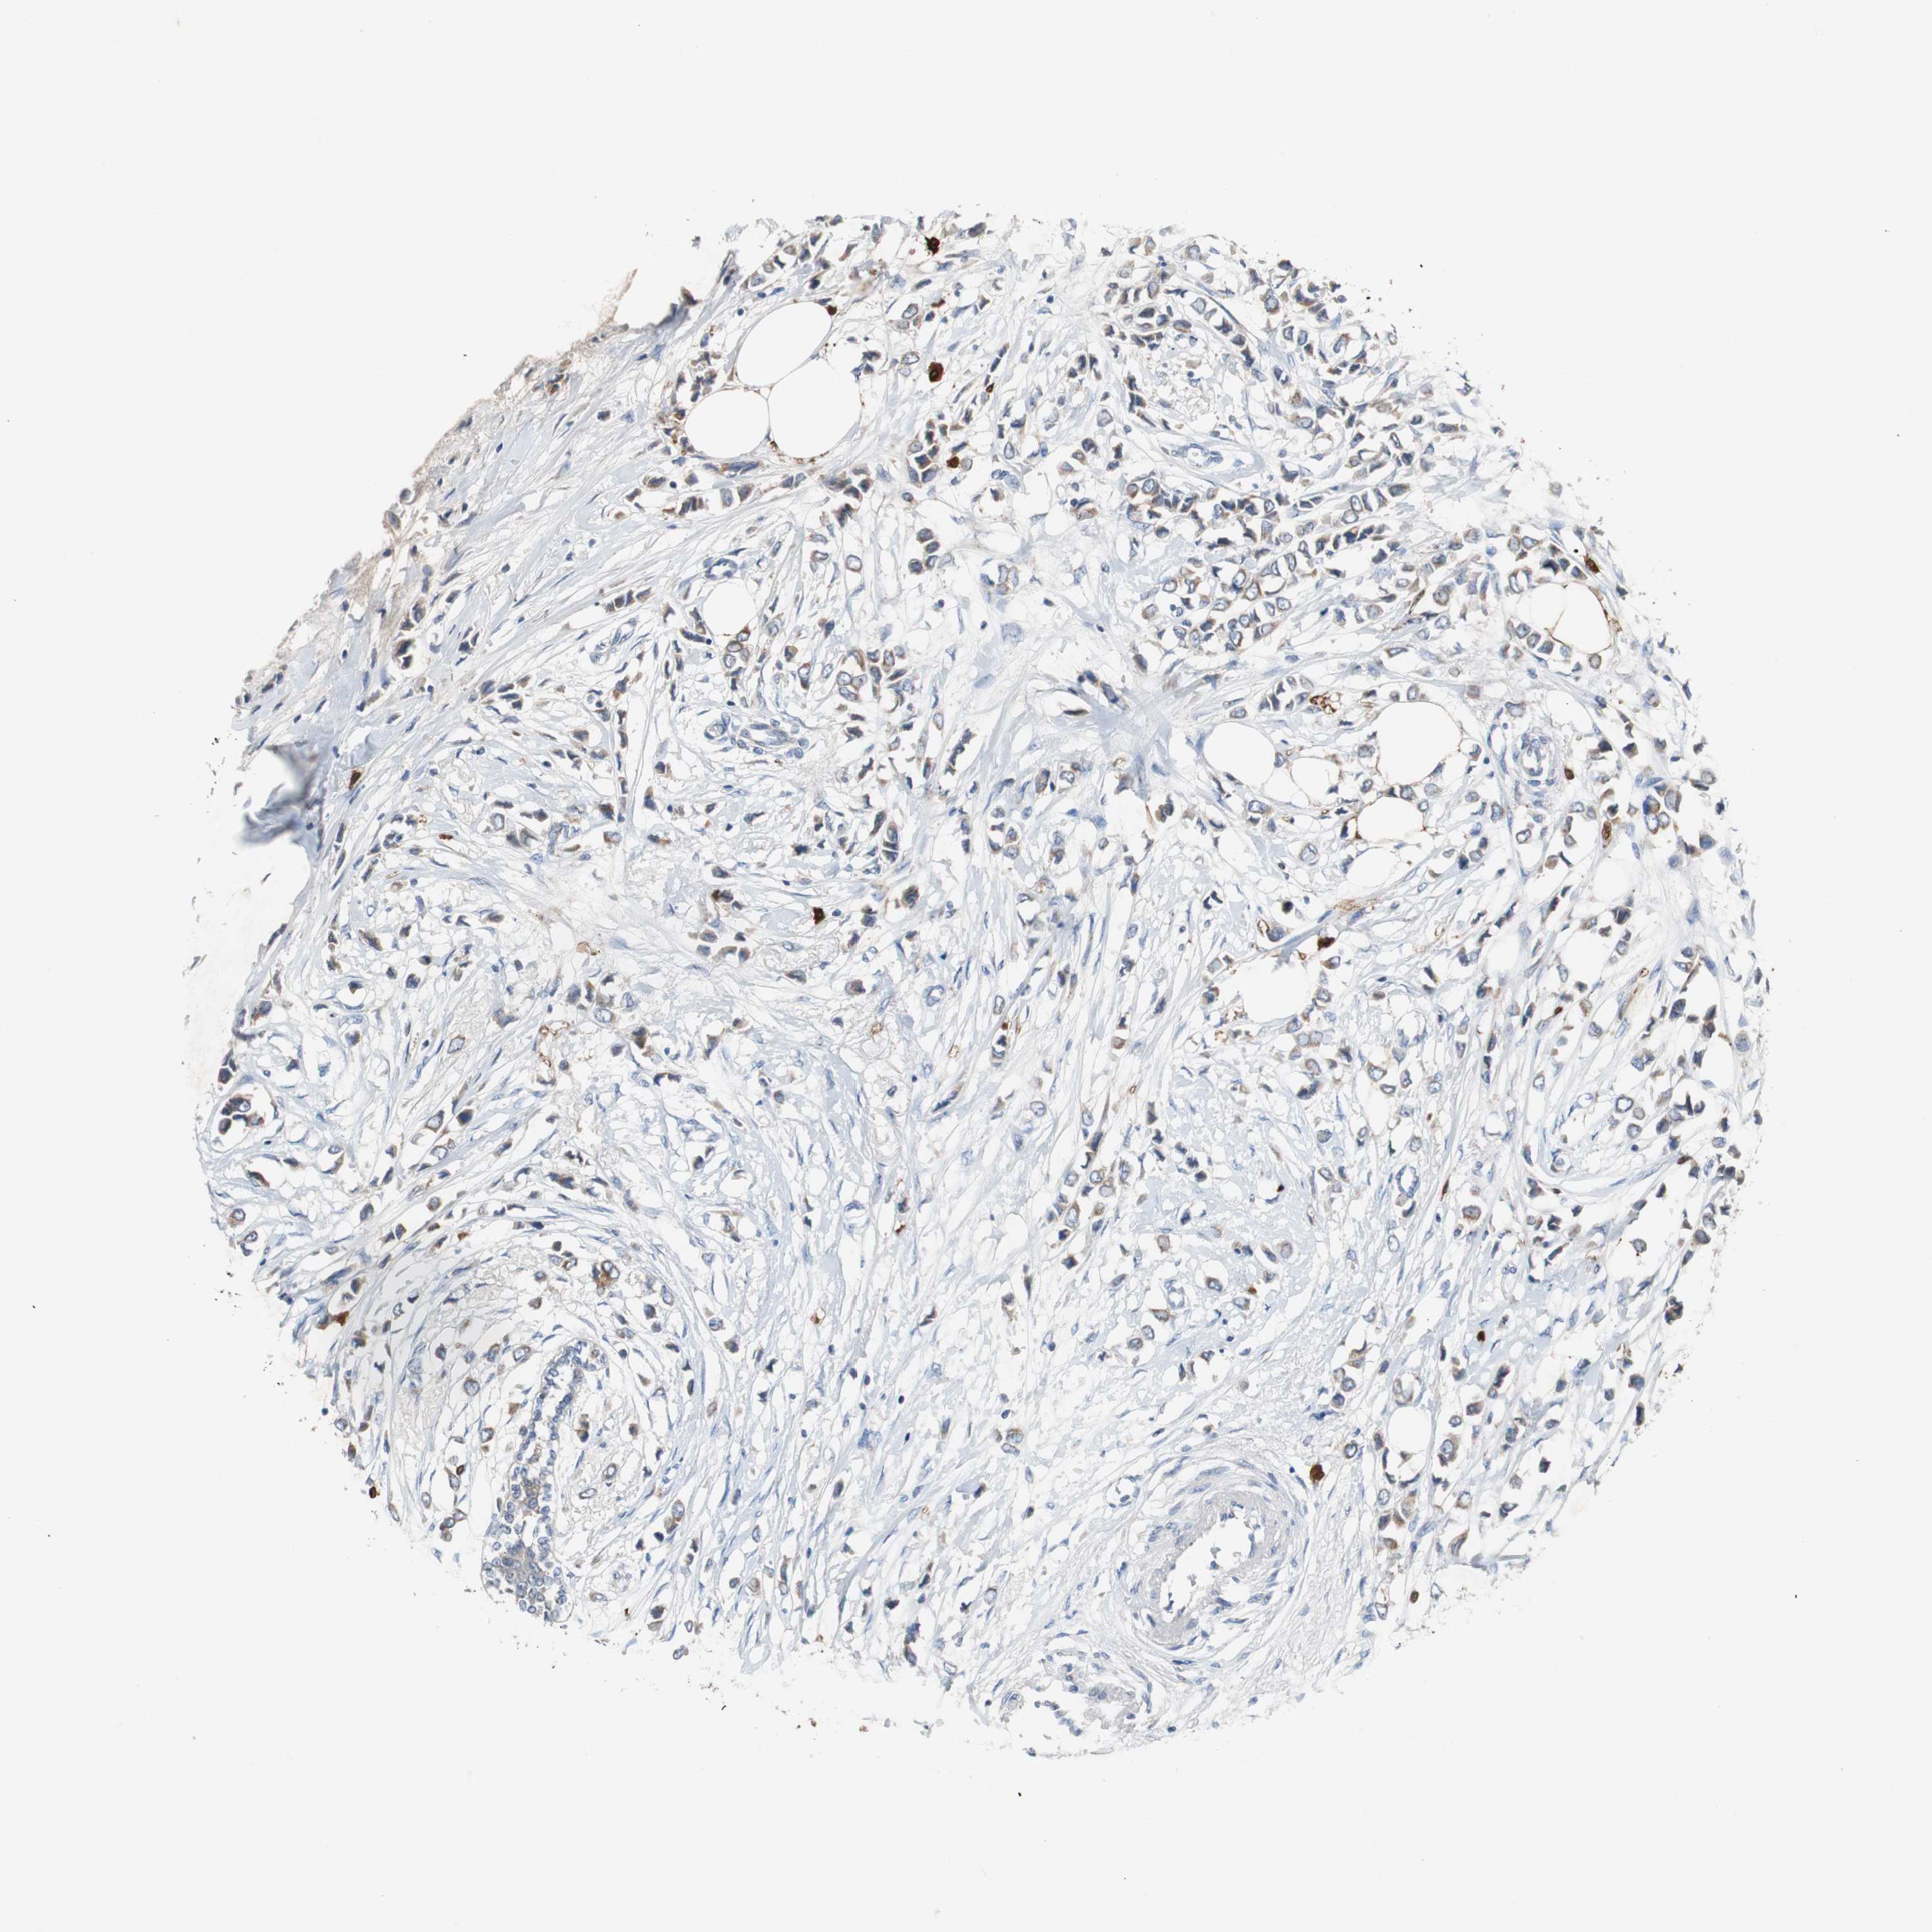

CANCER BREAST CANCER Show tissue menu

BRCA TCGA BRCA VALIDATION PROTEIN EXPRESSION